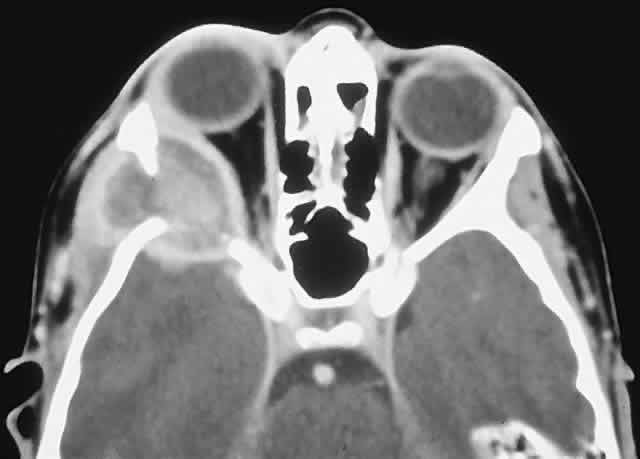

IMAGING. The CT appearance is of an expansile or permeating mass that shows mottled bone destruction (Fig. 11). There may be an associated soft tissue component.

Fig. 11. This 12-year-old boy experienced subacute left proptosis, vertical globe displacement, and lower lid edema. A. CT showed an expansile mass with mottled bone destruction of the orbital floor. B. Biopsy revealed a Ewing's sarcoma consisting of densely packed and mitotically active small round cells (hematoxylin-eosin, × 80).

HISTOPATHOLOGY. The tumor consists of firm, white tissue made up microscopically of sheets and clusters of uniform, small round cells. Cytoplasmic glycogen, as demonstrated by periodic acid-Schiff (PAS) positivity, is present in 90% of cases. Ultrastructurally, there is evidence of glycogen and a sparsity of organelles.18